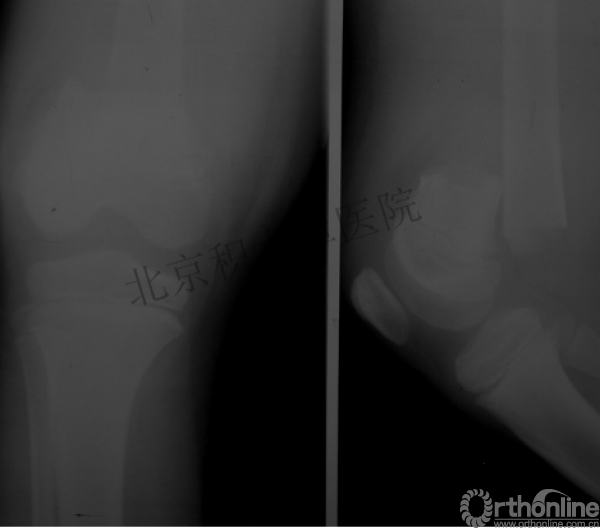

髁上骨折

跨骺板固定

伤后4年